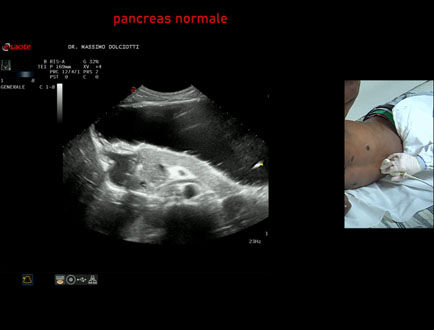

Data inserimento: 11/04/2025

Ecografia del: 26/03/2025

Strumento: Esaote MyLab Eight

Sonda: Convex Multifrequenza 1-8 MHz

Età Paziente: F 43 anni

Motivazione dell'esame: alvo alterno e pollachiuria.

Commento all'esame: le immagini ed il video documentano il pancreas, con regione cefalica, corpo e coda, ad ecostruttura e morfovolumetria regolare, di normale aspetto ipoecogeno.

Conclusioni: pancreas normale (normal pancreas).

Presentazione: Dr. Massimo Dolciotti - Ancona

Elaborazione digitale: Andrea Dini - Ancona